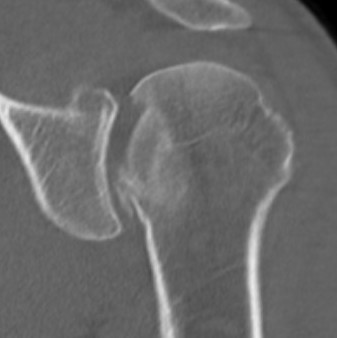

AP Xray

Abnormal overlap of humeral head on glenoid

Light-bulb sign - globular head secondary to internal rotation of the humeral head

Vacant Glenoid Cavity - > 6 mm space between humeral head and anterior rim of glenoid

Scapular lateral

Center of the humeral head must be centered on the Y / Mercedes sign

Y is formed by

- coracoid anteriorly

- scapular spine posteriorly

- scapula body inferiorly

Normal scapular lateral

Posterior shoulder dislocation

Posterior shoulder dislocations

Axillary Xray

Diagnostic - humeral head posterior to glenoid with evidence of reverse Hill Sachs